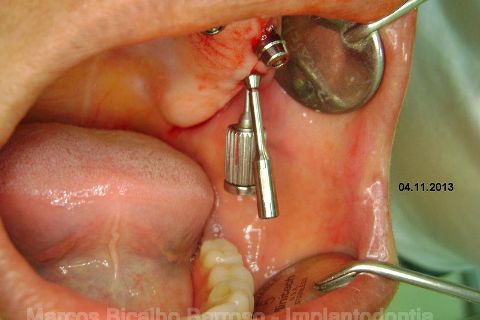

Atualização do caso clínico que já postei, "REABILITAÇÃO EM MAXILA ATRÓFICA COM IMPLANTES", um caso que inclui expansão do rebordo estreito com cinzel e martelo, expansores rosqueáveis, enxerto e instalação dos implantes distais inclinados tangenciando seio maxilar. Inclui esvaziamento do forame nasopalatino e preenchimento com biomaterial para instalação de dois implantes próximos dele. Cirurgia realizada em única sessão, com instalação dos 6 implantes. Para os colegas que não conheceram e/ou esqueceram da apresentação, este é o resumo do caso na fase cirúrgica.http://www.youtube.com/watch?v=BtvexFexRPA&hd=1

FASE PROTÉTICA DA REABILITAÇÃO EM MAXILA ATRÓFICA...incluindo a reabertura, instalação dos minipilares e PTR provisória reembasada sobre os cilindros de proteção.